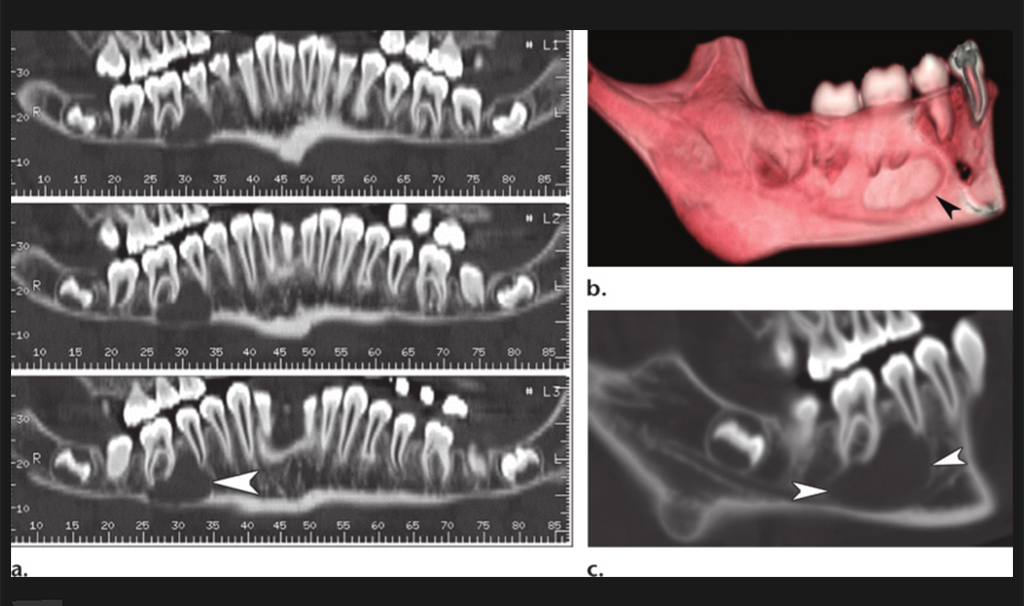

3D OPG

A panoramic radiograph is a panoramic scanning dental X-ray of the upper and lower jaw. It shows a two-dimensional view of a half-circle from ear to ear.

Mandible / Maxilla

This scan provides full madible evaluation for diganosis and teatment planning for any problem related to mandible, like fracture, cyst, nerve study, imacted tooth,